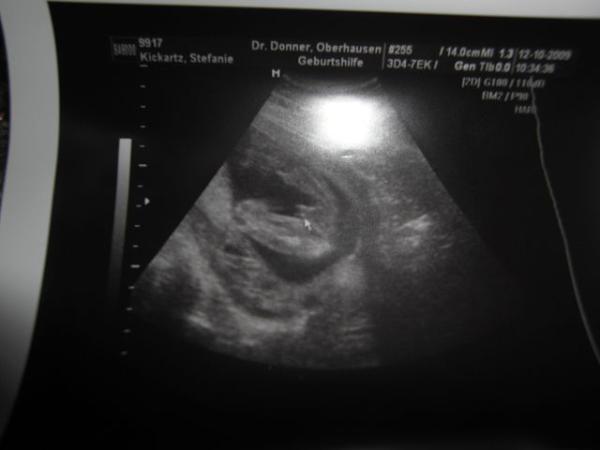

Ohne jetzt die anderen Antworten gelesen zu haben,ich würde sagen das ist ein Mädchen. Mein Junge sah so aus. lg Steffi

Bild zu

So ähnlich sieht mein Bild von meiner 90% Tochter auch aus;-) Tippe daher auf Mädchen...